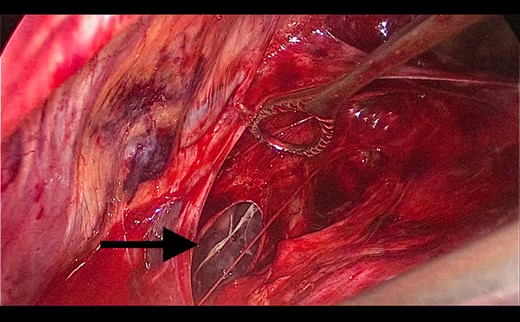

A 73-year-old male patient with a clinical history of COPD, lung emphysema and a 30-year smoking history was admitted to the ED due to a 24-h clinical picture of dyspnea immediately following a sudden bout of dry coughing. Physical examination showed a dyspneic patient, tachypnea of 25 rpm, heart rate of 85 bpm and blood Pressure of 135/75 mmHg along with central cyanosis. Chest exam showed a hyper-resonant right hemithorax along with reduced breath sounds. Initial chest X-ray revealed a large right-sided pneumothorax (Fig. 1). A right chest tube was placed in the ED. Emergency echocardiogram had no significant findings and spirometry showed suspected patterns of obstruction. Following patient stabilization, a high-resolution chest computed tomography (HRCT) was performed revealing extensive pan lobar emphysema throughout both lungs, para septal emphysema in both the anterior upper lobes and herniation of a left lung bullae through the anterior mediastinal pleura along with a right-sided pneumothorax with the chest tube in place with persistent air space (Fig. 2). The patient was taken to surgery where a right video-assisted thoracoscopic (VATS) approach showed severe lung emphysema and a contralateral herniated left lung bulla through the mediastinal pleura anterior to the pericardium (Fig. 3). Right pleurodesis was performed using Talc and a left posterior thoracoscopy showed a severe emphysematous left lung with a lingular herniated bulla to the right hemithorax through an anterior mediastinal pleural defect along with pleural adhesions (Figs 4 and 5). Thoracoscopic hernia reduction was performed along with bullectomy using 60 mm mechanical sutures (Fig. 6). Chest tubes were removed on POD 3 (right) and POD 4 (left). The patient had significant respiratory improvement and was discharged on POD 5.

Thoracoscopic view of transmediasinal herniation of pulmonary bulla to the right hemithorax (asterisk).